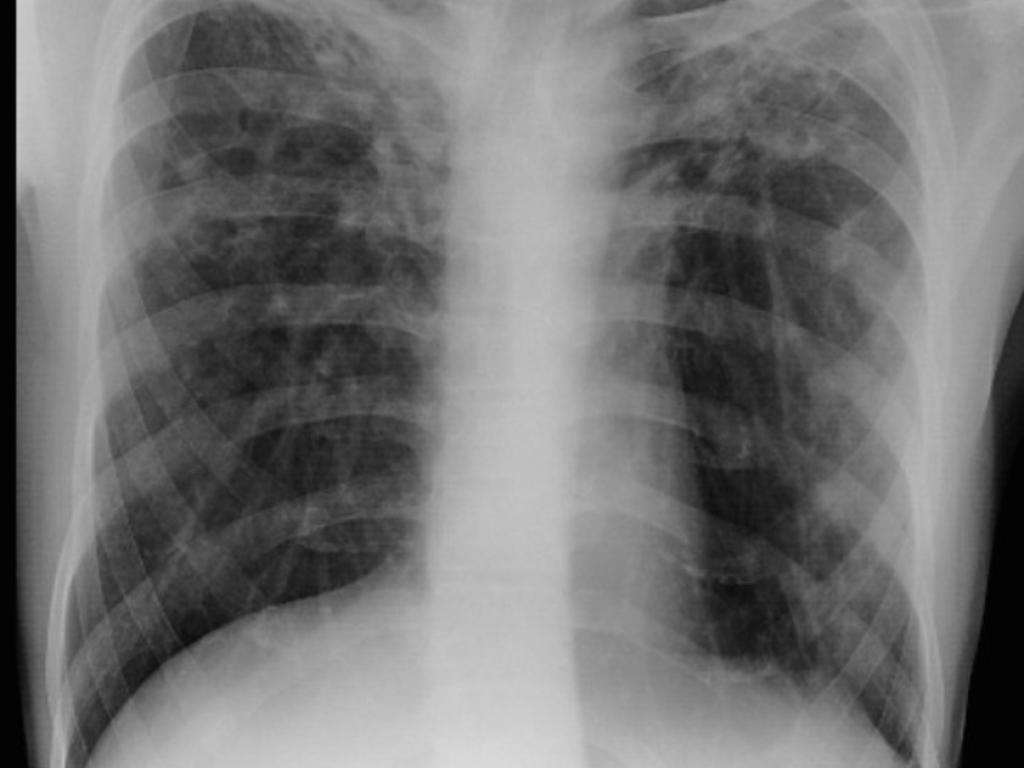

Abstract: Neutrophil accumulation is associated with lung pathology during active tuberculosis (ATB). However, the molecular mechanism or mechanisms by which neutrophils accumulate in the lung and contribute to TB immunopathology are not fully delineated. Using the well-established mouse model of TB, our new data provide evidence that the alarmin S100A8/A9 mediates neutrophil accumulation during progression to chronic TB. Depletion of neutrophils or S100A8/A9 deficiency resulted in improved Mycobacterium tuberculosis (Mtb) control during chronic but not acute TB. Mechanistically, we demonstrate that, following Mtb infection, S100A8/A9 expression is required for upregulation of the integrin molecule CD11b specifically on neutrophils, mediating their accumulation during chronic TB disease. These findings are further substantiated by increased expression of S100A8 and S100A9 mRNA in whole blood in human TB progressors when compared with nonprogressors and rapidly decreased S100A8/A9 protein levels in the serum upon TB treatment. Furthermore, we demonstrate that S100A8/A9 serum levels along with chemokines are useful in distinguishing between ATB and asymptomatic Mtb-infected latent individuals. Thus, our results support targeting S100A8/A9 pathways as host-directed therapy for TB.